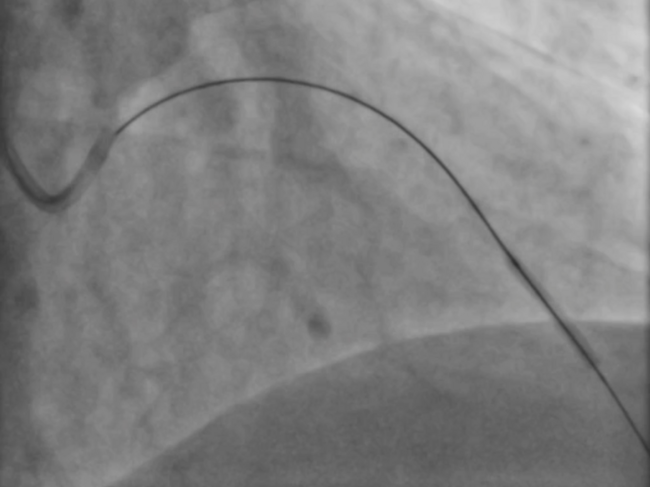

Treatment of LAD With Investment Procedure in a Patient With Failed CTO-PCI

Video supplement to “Treatment of LAD With Investment Procedure in a Patient With Failed CTO Attempt With TIMI 0 Flow,” by Barman et al. (August 2021 Clinical Images).

A 48-year-old male patient with a known diagnosis of hypertension presented after 6 months of chest pain. The following coronary angiography video series shows the diagnosis and treatment of a chronic total occlusion (CTO) of the left anterior descending (LAD) coronary artery from the mid-region.